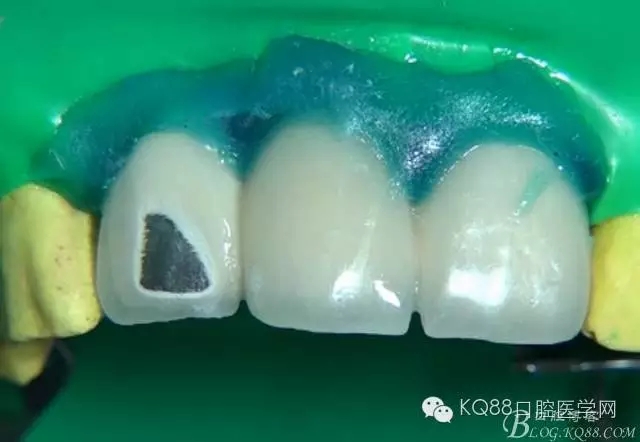

第二步上橡皮障隔濕并保護軟組織。

第三步封閉橡皮障邊緣

第十步上遮色樹脂遮蓋金屬顏色。一次不要涂布過厚,分兩到三次完全遮蓋金屬顏色,每次光照30秒。